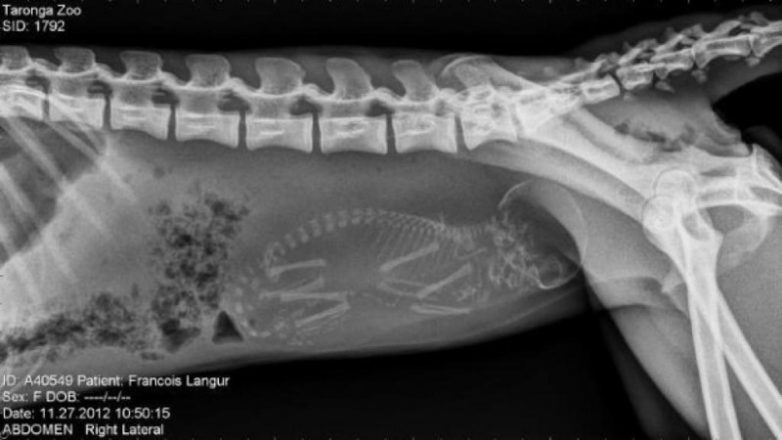

Беременные животные под рентгеном

Так выглядят рентгеновские и ультразвуковые снимки беременных животных.

Беременная обезьяна